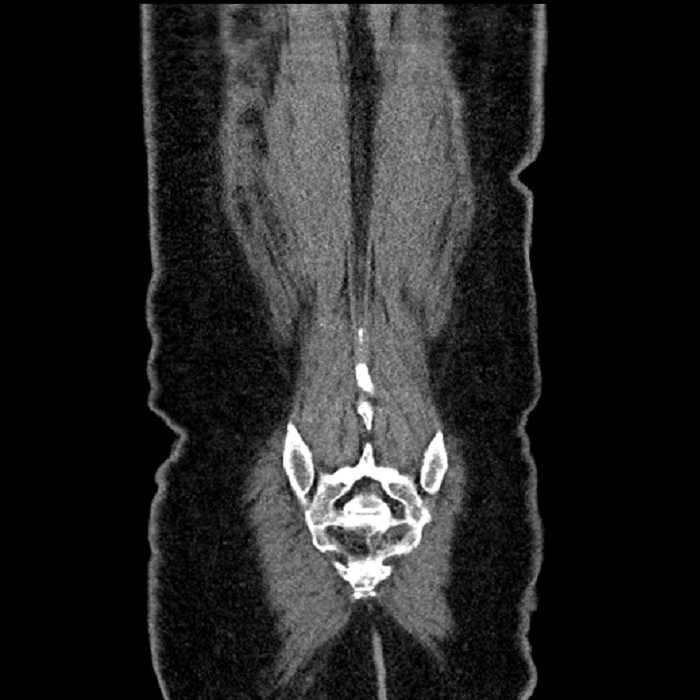

• Ankylosis of both sacroiliac joints

Hepatic abscess showing the double target sign with low density internally surrounded by a thin inner enhancing rim (red arrow) and ill-defined outer low density rim (yellow arrow). Blue arrow indicates an internal septation. Red arrows: additional smaller subcapsular abscesses. Red arrow: focal contained perforation associated with diverticulitis.